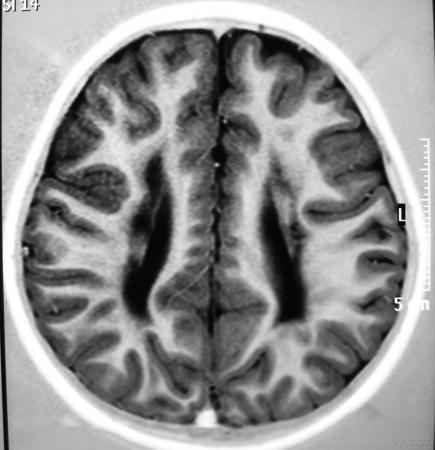

影像学发生于侧脑室周围,侧脑室扩大,脑白质减少。扩大的侧脑室外缘常不规则为其特点,多为双侧脑室同时扩大。脑白质减少,脑皮层与脑室侧缘相近。MRI T1呈低信号,T2呈高信号。